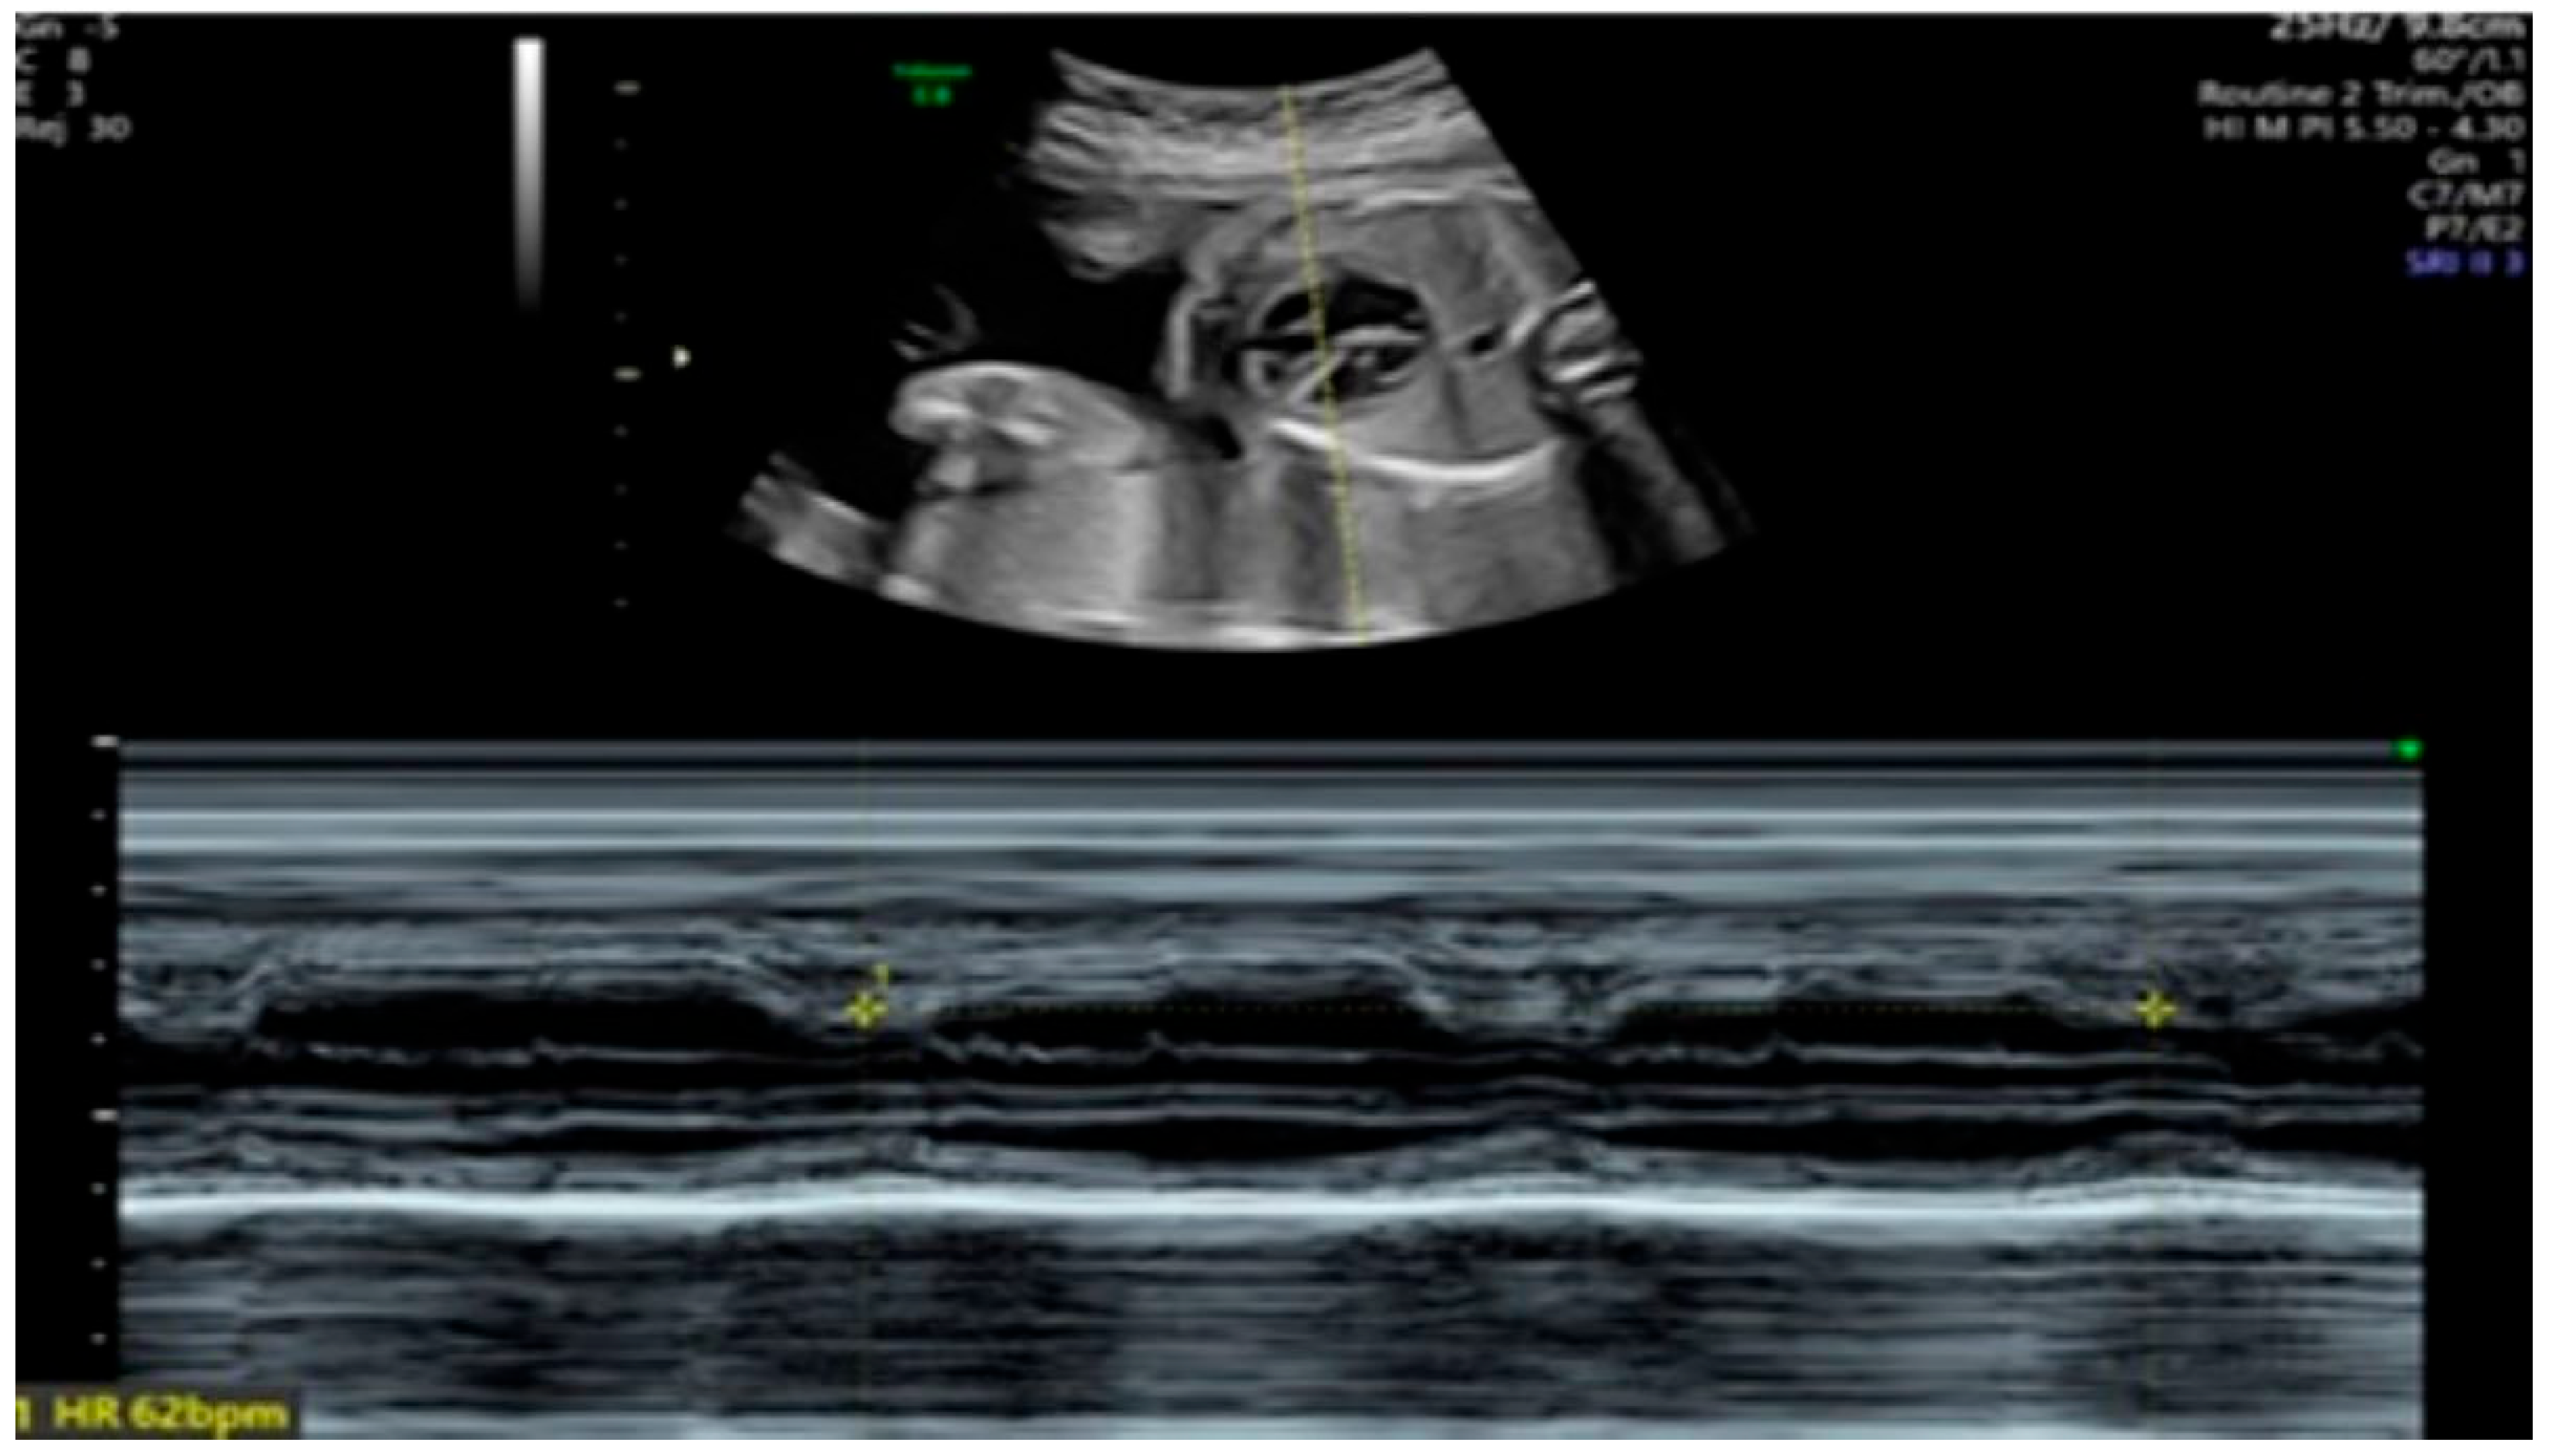

| 26 + 0 | Start of dexamethasone 4 mg/day | 60 | SF increased from 34% to 47%, but qualitative contractility decreased | Mild edema; no beta- agonists used |